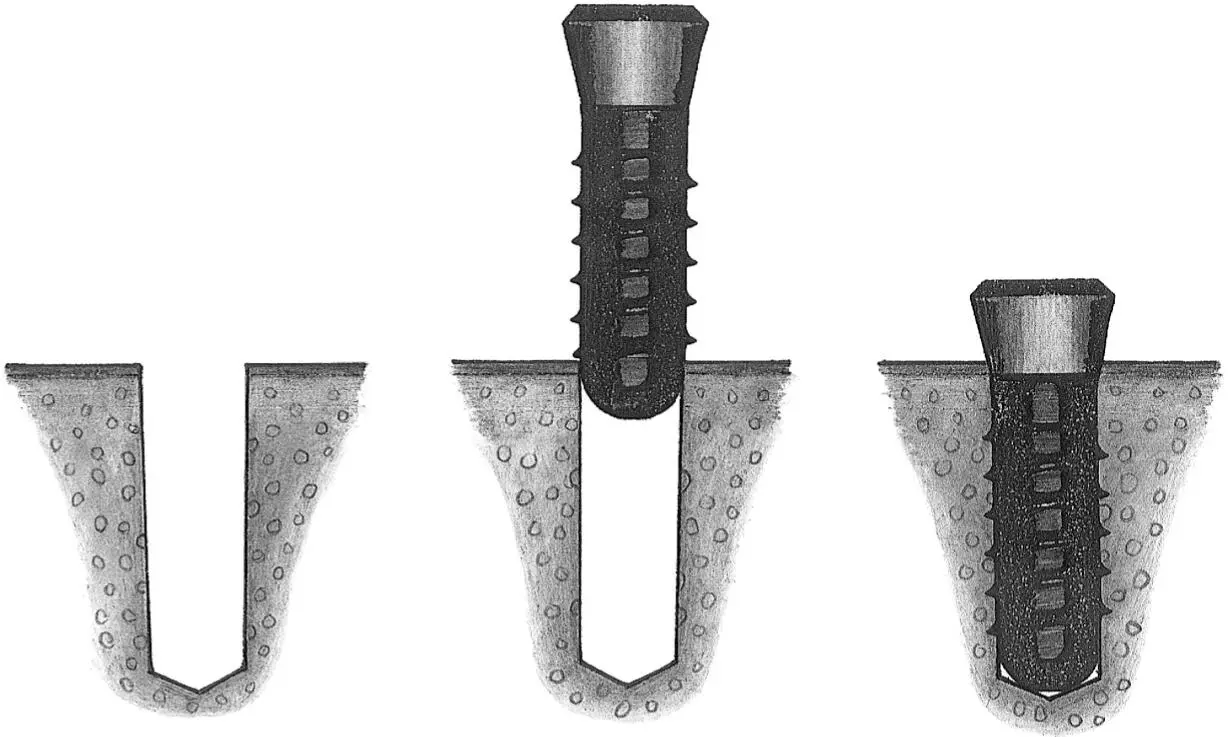

Fig 1-3Correction of the position and axis of the implant site preparation.

Fig 1-3a The preparation of the implant site begins with the use of the nos. 1 and 2 round burs to mark the position of the implant site.

Figs 1-3b and 1-3c Any required changes to the marking made with the first round bur can be accomplished with the no. 2 round bur, as shown in this occlusal view. These initial steps for the preparation of the implant site ensure the correct implant position orofacially and mesiodistally.

Fig 1-3d After the use of the first pilot drill (A) , a 2.2-mm-diameter guide pin is used to check the axis and depth of the implant preparation (B) . Any incorrect axis orientation can be adjusted with the same 2.2-mm-diameter pilot drill (C and D) and then followed with the 2.8-mm-diameter spiral drill (E) .